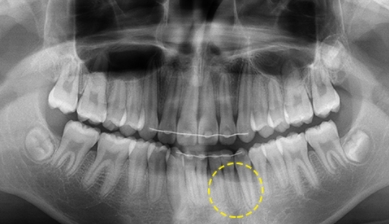

3. 치아종

치아종은 치아가 작은 덩어리로 여러 개 뭉쳐잇는 것을 말하며 복합 치아종과 복잡 치아종으로 나눠집니다.

치아종 제거 후 치아교정을 통해 맹출되지 못한 치아를 맹출 시킵니다.